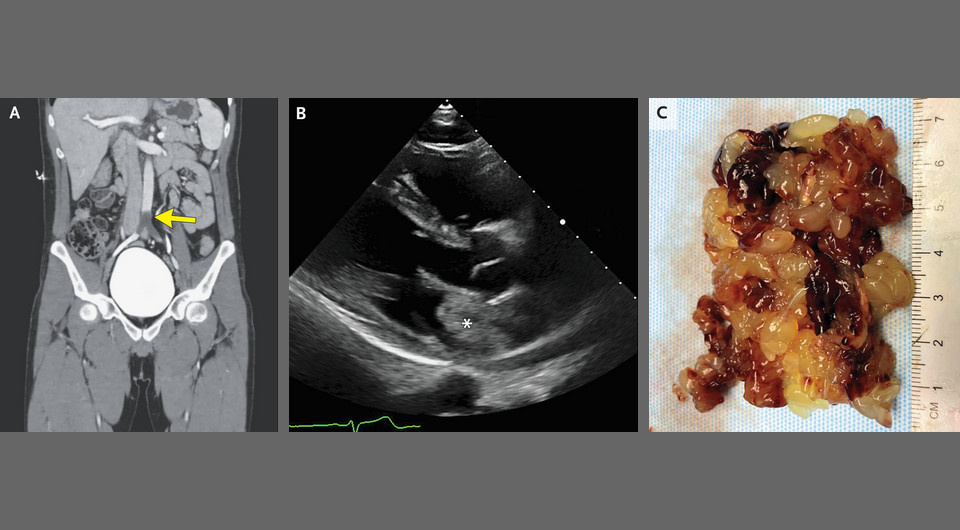

В неотложное отделение американской клиники поступил 26-летний мужчина с жалобами на остро возникшую сильную боль в ногах и невозможность двигать левой ногой. Ранее он проблем со здоровьем не имел. При осмотре наблюдалось полное отсутствие моторных функций левой ноги, пульс на дорсальных артериях стоп плохо прощупывался с обеих сторон. УЗИ с цветной допплерографией показало отсутствие кровотока в дистальном отделе аорты. Компьютерно-томографическая ангиография вывила седловидную эмболию аорто-подвздошного соединения. Пациенту выполнили экстренную эмболэктомию, в ходе которой извлекли из сосуда желеобразное образование. Врачи Чираг Буч (Chirag Buch) и Нилам Сони (Nilam Soni) из Научно-медицинского центра Техасского университета в Сан-Антонио поделились этим случаем в New England Journal of Medicine.

Chirag A. Buch, and Nilam J. Soni / NEJM, 2025

На последующей плановой эхокардиограмме визуализировалось гетерогенное образование в левом предсердии. Мужчину прооперировали и извлекли из этого предсердия рыхлое ворсинчатое разрастание. Его гистологическое исследование выявило обильный мукополисахаридный матрикс с рассеянными островками клеток. На основании данных обследования пациенту поставили диагноз острой окклюзии брюшной аорты из-за эмболии фрагментом миксомы левого предсердия — относительно редкой доброкачественной опухоли сердца. Восстановительный период у мужчины прошел без особенностей, к моменту повторного осмотра через два месяца он уже вернулся к работе.